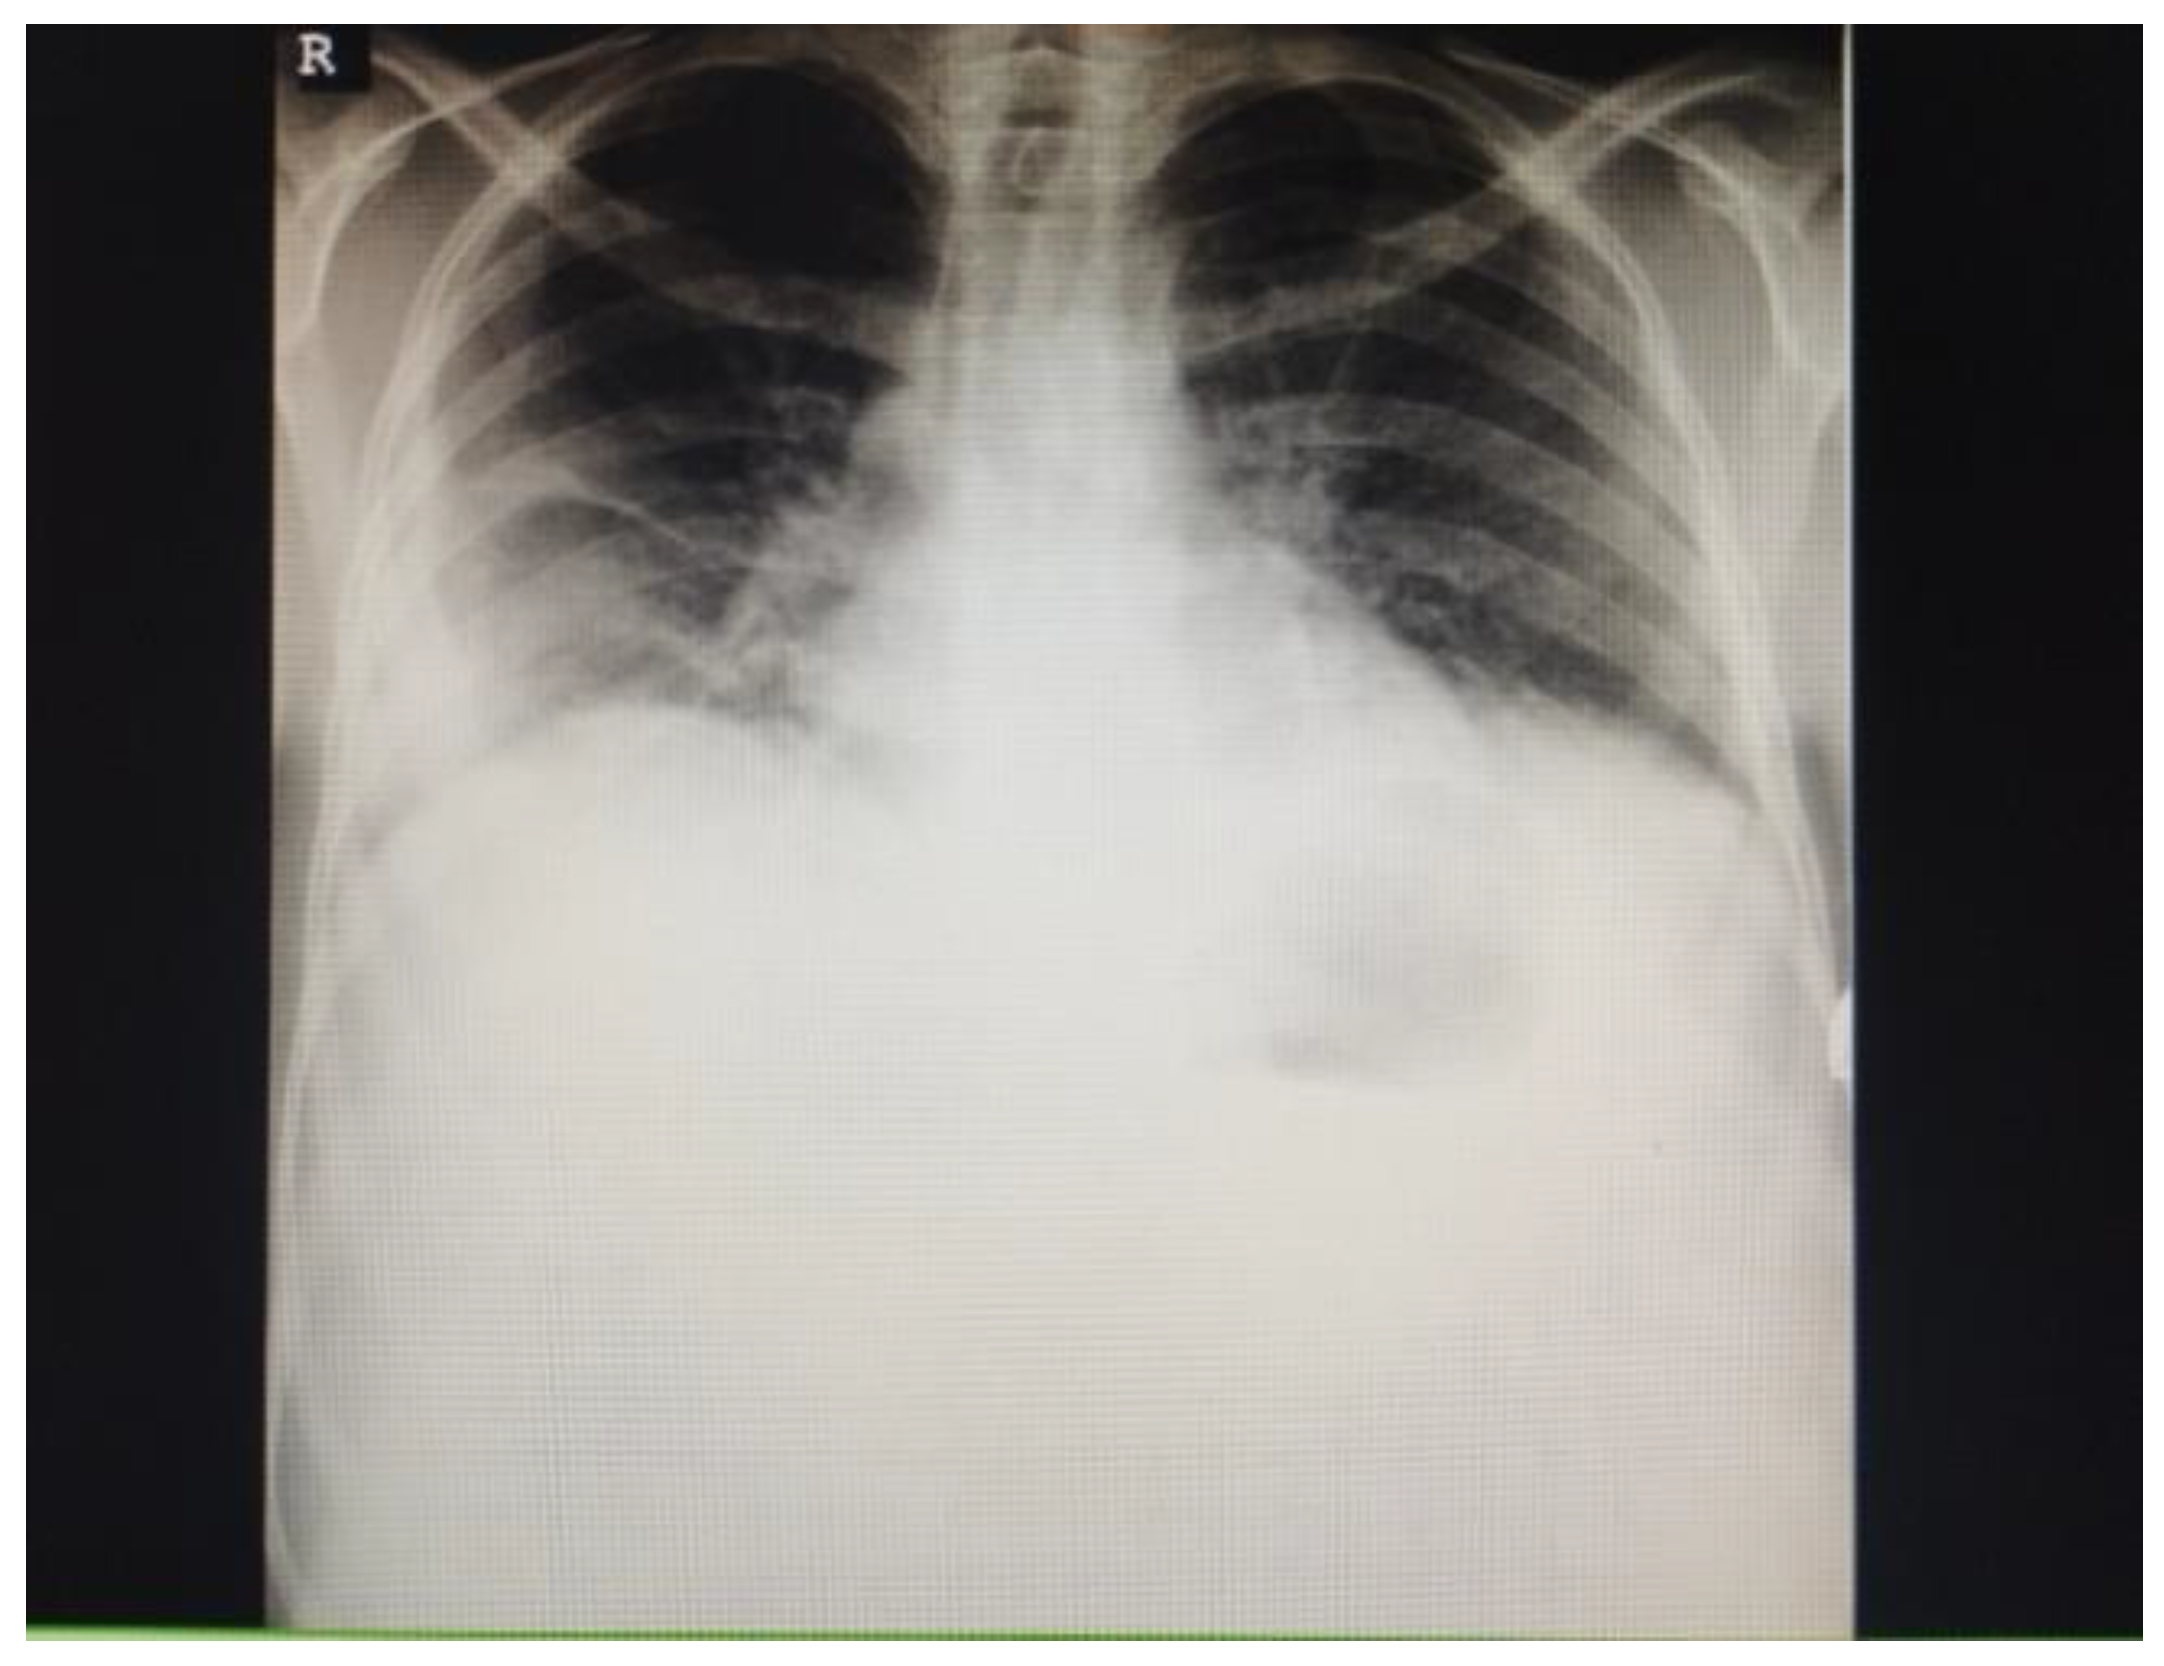

2. Case Presentation